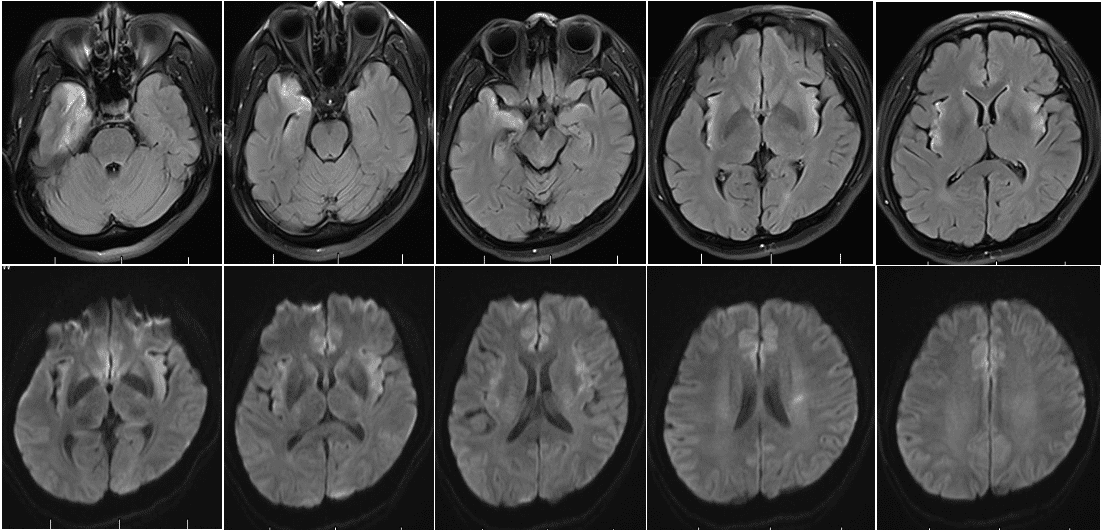

复查头MR(2025-12-30 我院) :左侧颞极、海马、双侧岛叶额叶可见不规则片状或条状长T1、长T2信号影。 影像诊断:双侧颞叶、额叶脑沟走行病变,符合脑炎诊断。